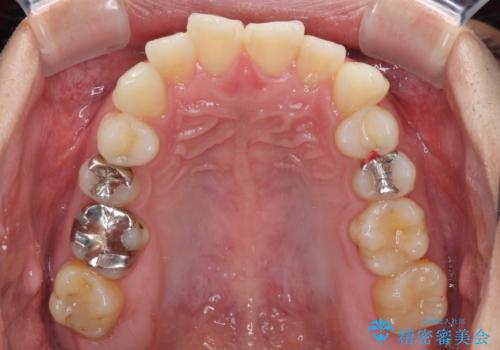

虫歯が大きかったため、クラウンによる補綴治療が必要になる旨をお伝えしたところ、矯正治療にも興味があるとのことでした。

短期間で手間のかからない方法がご希望でしたので、ワイヤー装置による矯正治療を行うこととし、矯正治療後に右奥2歯をセラミッククラウンにて補綴することとしました。

セラミッククラウンによる補綴治療と矯正治療の双方が必要となる場合、矯正治療前の処置や歯の移動中に必要な処置など、二種類の治療を同時にチェックすることがとても重要となります。

当法人では、1つの医院で全ての診療を進めることができるため、このような方には大変お勧めです。